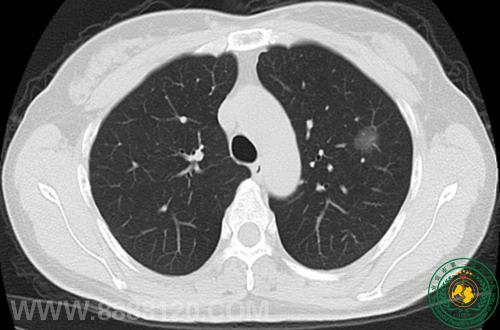

病例51病员无身体不适,例行体检。

DR 未见异常,CT示左肺固有上叶一磨玻璃密度样结节,直径约1.6cm,考虑为肿瘤性病变可能。术后病检:符合原位腺癌(细支气管肺泡癌),支气管断端未查见肿瘤累及。